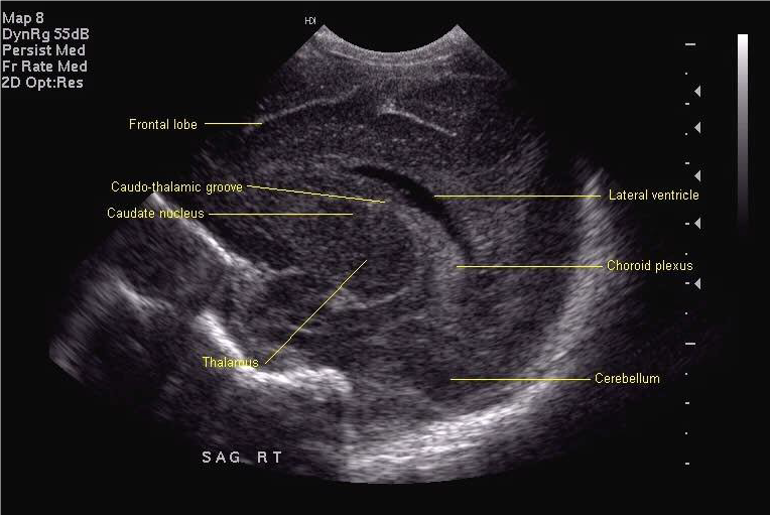

Standard views for cranial ultrasonography of the newborn

Lateral sagittal (to be labelled "left" or "right")